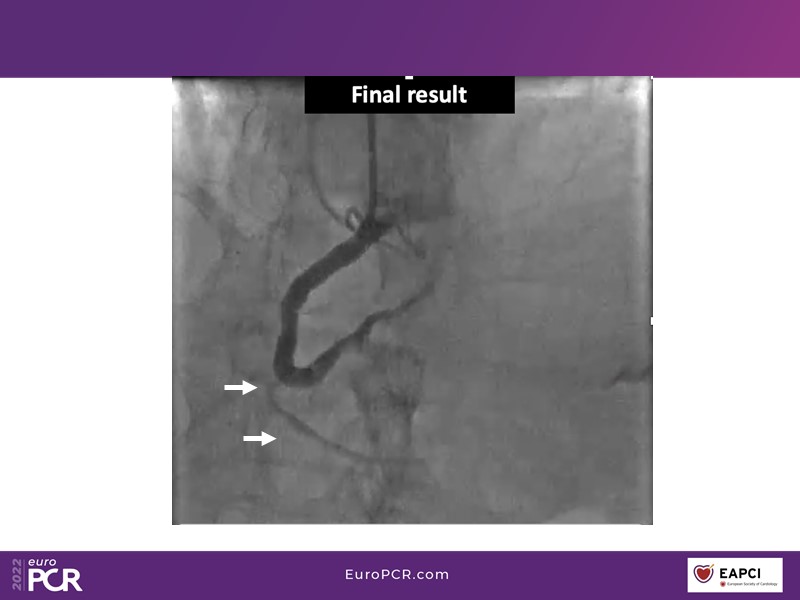

- To find out more about the application and mechanism of a sirolimus coated balloon for coronary artery disease treatment with case presentations in complex settings

- To understand how useful is a DES and DCB stent platform in complex coronary artery disease settings with case demonstrations and follow-up in diabetes mellitus